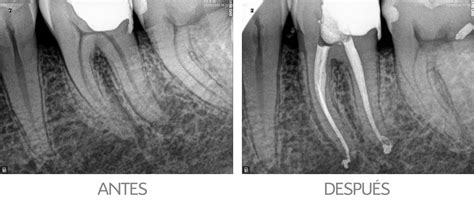

Endodoncia rotatoria

¿Qué es una endodoncia dental? Fácil y rápido